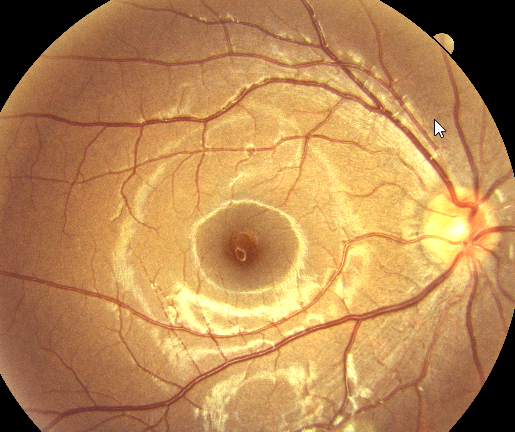

Macular Degeneration

29 January 2024

What is Macular Degeneration? Age-Related Macular Degeneration (AMD) is a common eye condition where the central portion of the retina, known as the macula, gradually loses its ability to see. Often associated with the aging process, AMD tends to be more prevalent among individuals ...